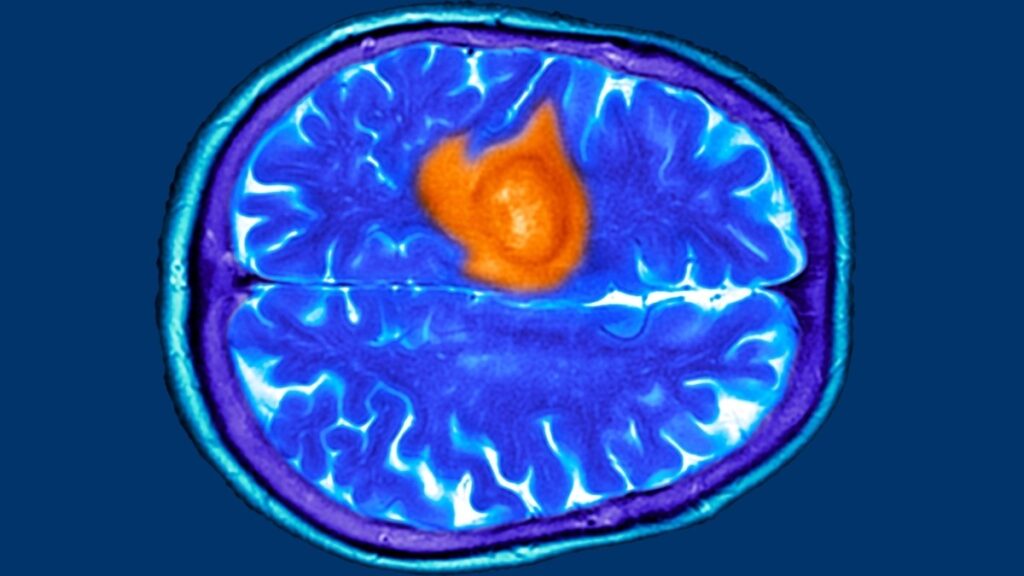

Treat brain cancer.

If the doctor confirmed a diagnosis of brain cancer, they would developed a treatment plan for and with you. The type of treatment depends on what type of brain cancer you had an how severe it was.